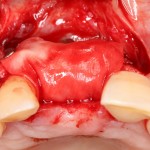

Другой вариант. Имплантируем, но существующего объема костной ткани недостаточно для получения адекватного эстетического и функционального результата:

Поэтому мы используем мембрану Geistlich BioGide и всё ту же аутокостную стружку: